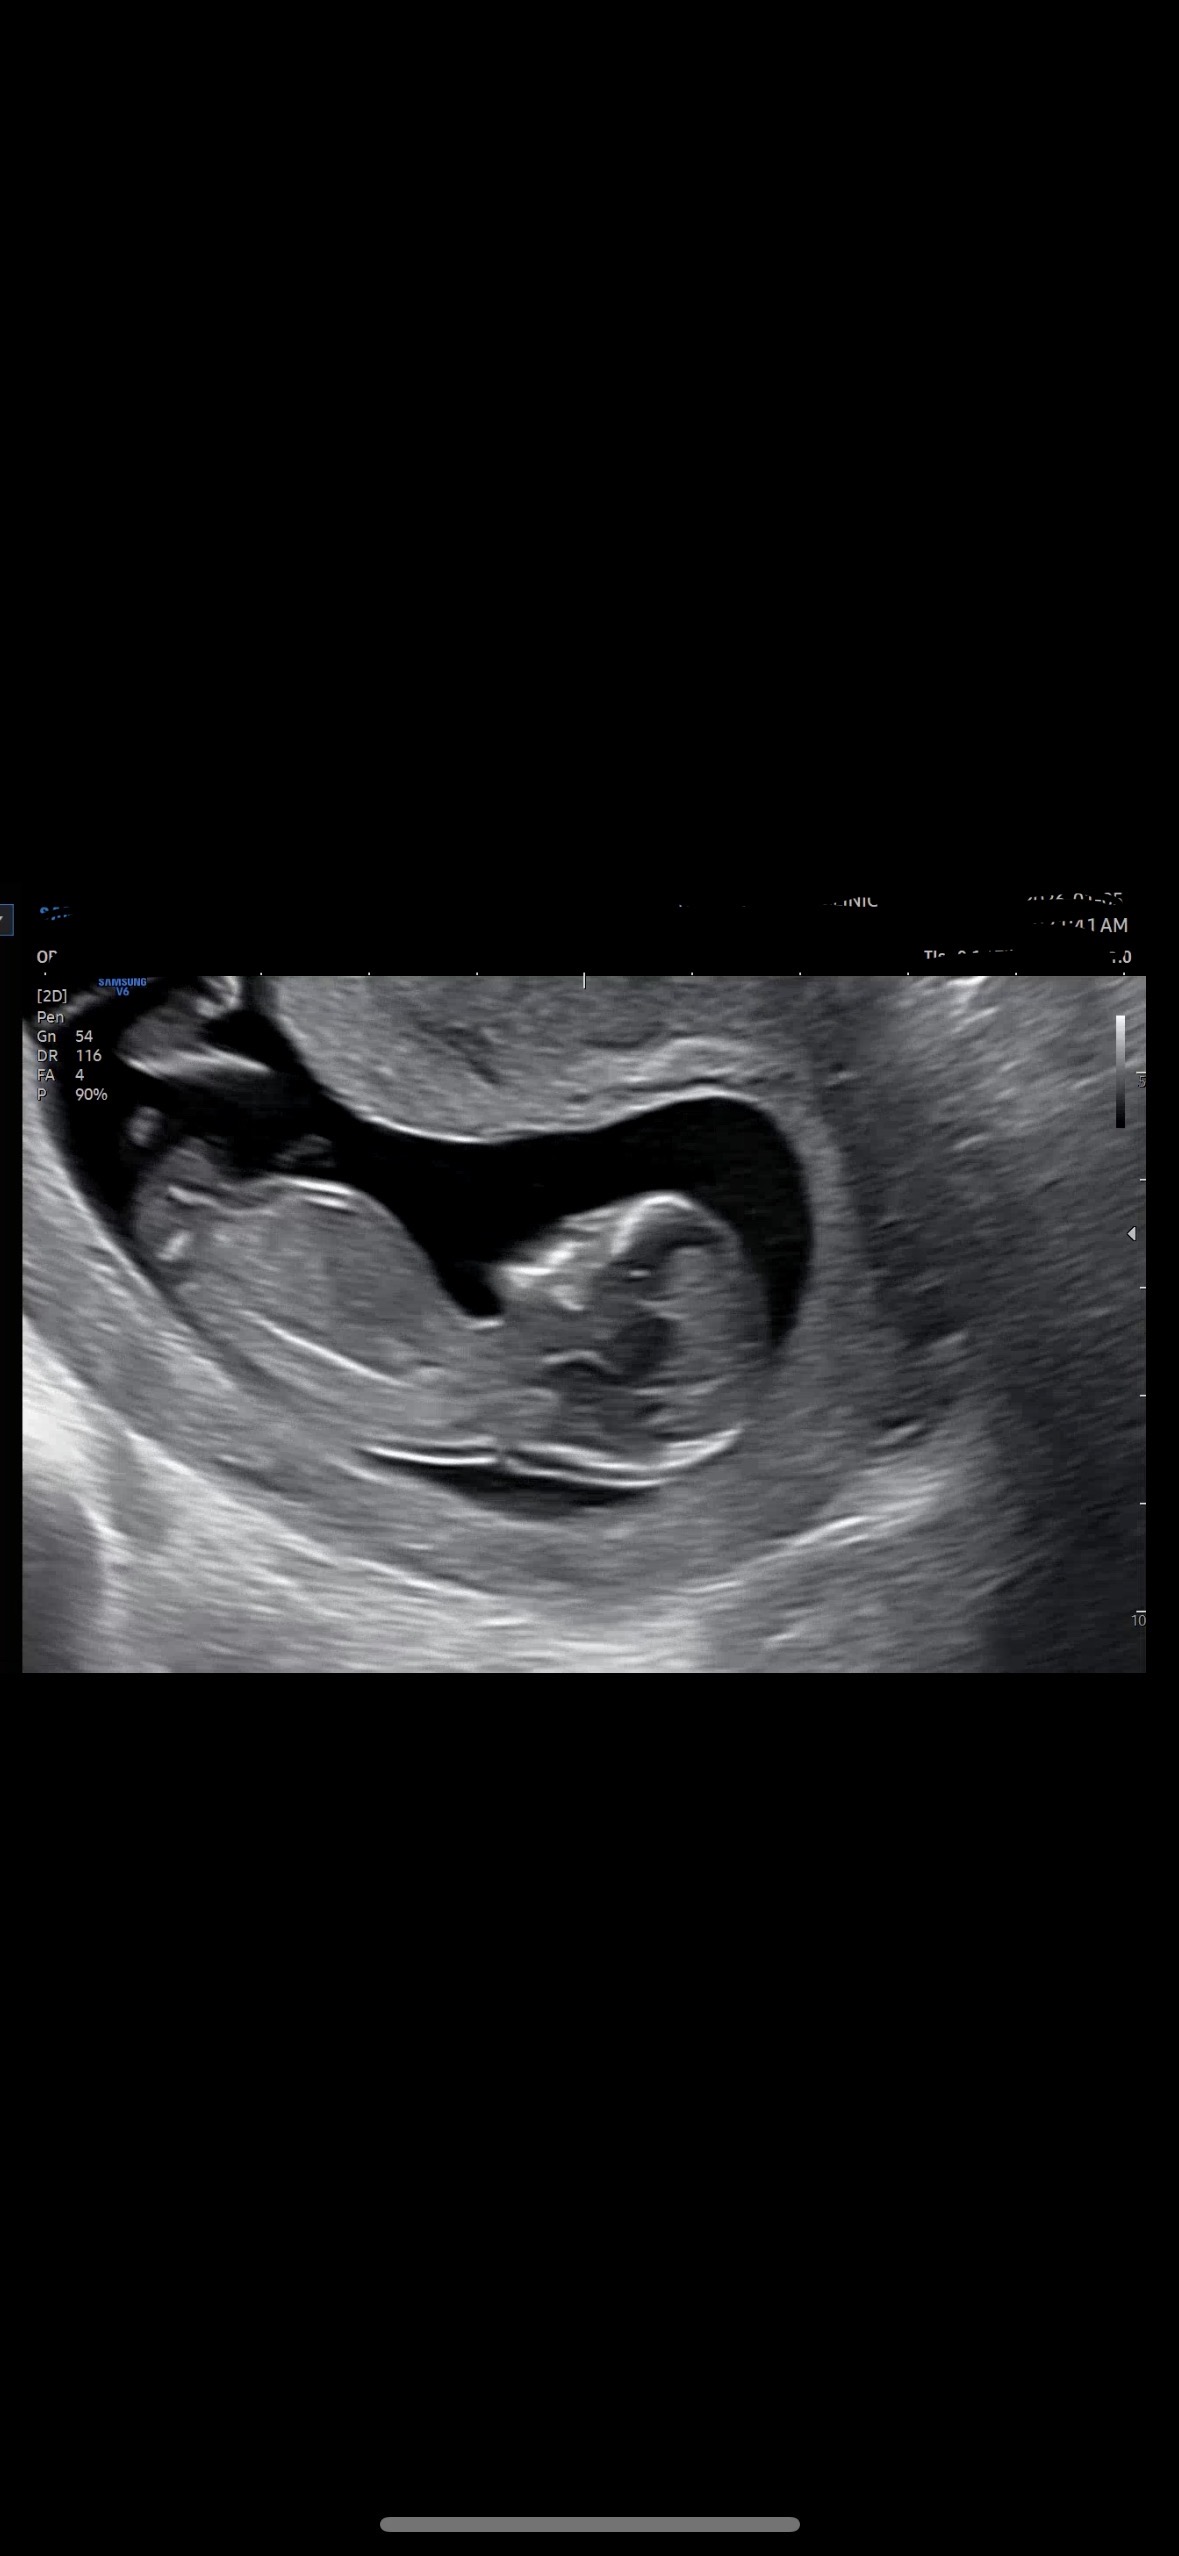

12주3일 성별 각도법 부탁드려요!

사진을 잘못 올려 재업합니다ㅠ-ㅠ.... 마구마구 참견해주세요!